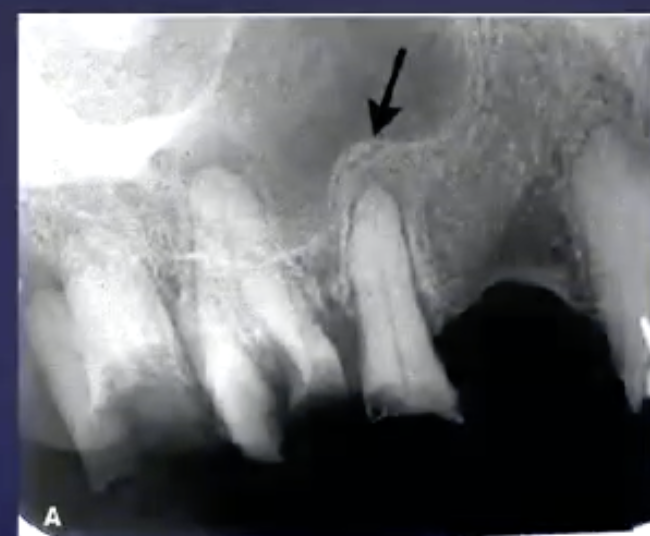

what’s the arrow pointing to

periosteal new bone formation